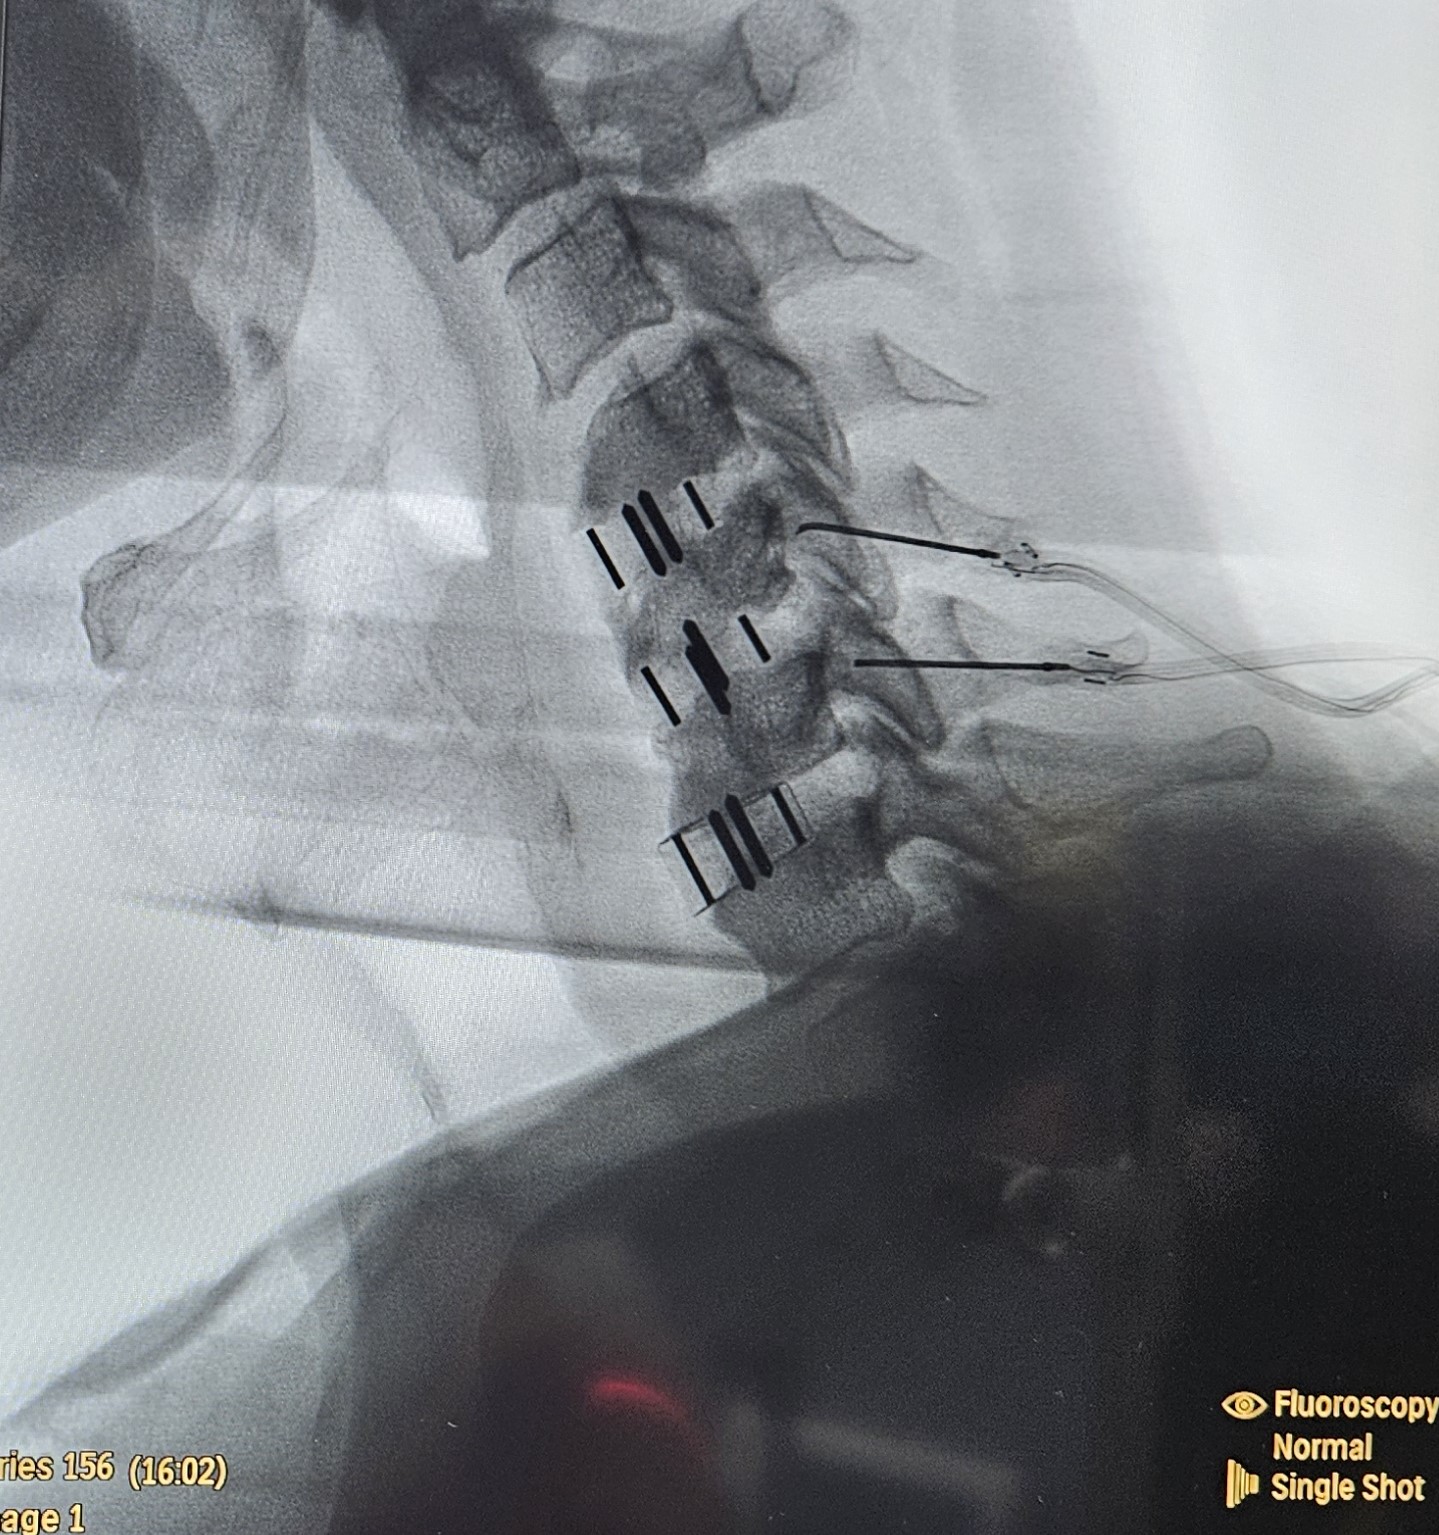

- Χειρουργική παρέμβαση επί επίμονου ριζιτικού πόνου, αδυναμίας άνω άκρων ή επί ανάπτυξης μυελοπάθειας

- Εγχύσεις στις αρθρώσεις της αυχενικής μοίρας

- Κατάλυση των αυχενικών αρθρώσεων με χρήση ραδιοσυχνοτήτων

- Επισκληρίδια έγχυση επί υποκείμενης κήλης μεσοσπονδυλίου δίσκου με ή χωρίς ριζιτική προσβολή